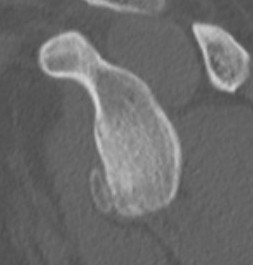

CT scan

Bony bankart

Bony bankart 3D CT with humeral head subtraction